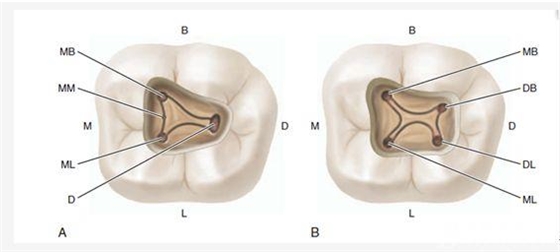

H、關(guān)于下磨牙MM根管的重視問(wèn)題:

1、查閱各種文獻(xiàn),MB2的發(fā)生率在52-96%之間,治療時(shí)遺漏是上頜磨牙根管治療失敗的主因,2、一般位于MB1根管口與腭根管口方向的0.5-5mm范圍內(nèi),而大多數(shù)都位于MB舌側(cè)的1-3mm處,其中2mm以內(nèi)占85.7%,3、MB1-P根管口連線與MB1-MB2根管口的連線夾角大部分(74.3%)在30度以內(nèi);4、MB2的尋找大部分需要去除相應(yīng)部位的牙本質(zhì);5、當(dāng)找到的MB根管口呈“長(zhǎng)線型”且有深色凹線向舌側(cè),或者找到的MB根管口明顯偏頰多提示有MB2的可能;6、DOM(牙科手術(shù)顯微鏡)的使用有助于找尋MB2;

D、“中心平衡對(duì)稱法則”:主根管在牙根中的分布符合“中心平衡對(duì)稱法則”,牙齒在進(jìn)化過(guò)程中,跟其它大自然的規(guī)律一樣,即根管基本位于牙根橫斷面的中心,類似于髓室也是(或者鈣化前曾經(jīng)也是)位于牙冠橫斷面的中心一樣,如果你發(fā)現(xiàn)的根管明顯不位于它支配牙根的中心,基本可以提示有另外一個(gè)根管的存在,類似于花園草坪上的噴水孔,分布應(yīng)該是均勻的,比如除上頜磨牙外,如果髓室底非中央位置發(fā)現(xiàn)一個(gè)根管口,在其對(duì)側(cè)相應(yīng)位置常有另一根管口;